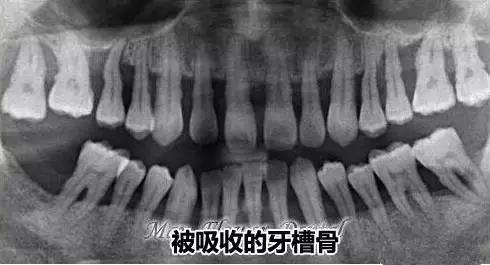

牙槽骨嚴(yan) 重萎縮,牙齒鬆動嚴(yan) 重可能是需要拔牙的